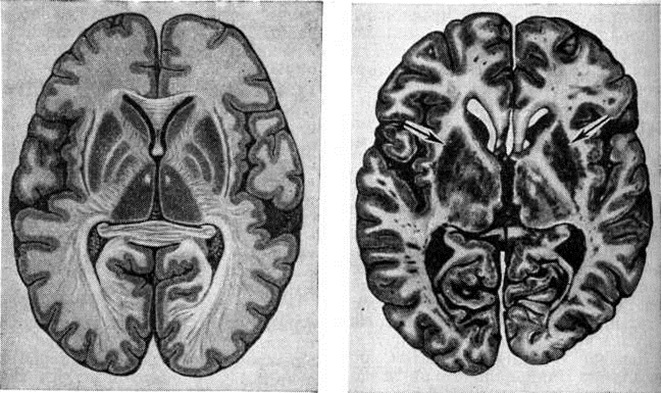

Печень вследствие атрофического цирроза уменьшена и бугриста (рисунок 4); участки нормальной ткани чередуются с участками некротическими, дегенерирующими и с островками регенерации; обильное новообразование сосудов приводит к появлению анастомозов между ветвями воротной и нижней полой вены. ПатогенезОсновную роль в патогенезе гепато-церебральная дистрофия играют генетически обусловленные нарушения обмена белков и меди. Нарушение синтеза белков ведёт к гипераминоацидурии (смотри Аминоацидурия) и гипопротеинемии (смотри Протеинемия), страдает и обмен нуклеопротеидов. Особенно большое значение имеет уменьшение церулоплазмина — белка, содержащего медь и обладающего ферментативными свойствами оксидазы (смотри Кровь, биохимия). В результате медь оказывается лишь рыхло связанной с альбумином и аминокислотами крови, легко отщепляется от них, в большом количестве выделяется с мочой (гиперкупрурия) и откладывается в тканях, главным образом в печени, головном мозге (подкорковые узлы) и роговице. Избыток свободной меди угнетает активность окислительных и некоторых других ферментов, что приводит к гибели клеток. Поражение печени с распадом её ткани и снижением барьерной функции ведёт к аутоинтоксикации продуктами гепатолиза и чужеродными продуктами, поступающими из кишечника (в частности, содержащими аммиак). В результате образования гистаминоподобных и других веществ ангиотоксического действия наступают тяжёлые расстройства кровообращения, усиливающие имеющуюся тканевую гипоксию. Вследствие этого гибель ткани отмечается прежде всего в местах, где потребность в кислороде особенно велика, то есть в головном мозге, особенно в чечевичных ядрах и коре больших полушарий. Кроме того, образуются и цитотоксические вещества, действующие непосредственно на элементы нервной ткани. Клиническая картинаГепато-церебральная дистрофия начинается в детском или молодом возрасте и имеет хронический прогрессирующее течение. Во многих случаях появлению симптомов поражения нервной системы предшествуют висцеральные расстройства в виде нарушения деятельности печени и желудочно-кишечного расстройств (желтуха, боли в правом подреберье, диспептические явления). Порой развивается выраженный гепато-лиенальный синдром (смотри). Чем сильнее страдает печень, тем раньше начинается и быстрее течёт заболевание. Со стороны нервной системы на первый план выступают экстрапирамидные симптомы в виде мышечной ригидности, гиперкинезов (рисунок 5) и расстройств психики. Пирамидные симптомы могут быть, но чаще отсутствуют. Чувствительность обычно не расстроена. Типичным симптомом болезни является кольцо Кайзера — Флейшера — отложение по периферии роговой оболочки содержащего медь зеленовато-бурого пигмента (цветной рисунок 7); оно более выражено при поздних формах заболевания. Иногда отмечается желтовато-коричневая пигментация кожи туловища и лица. Часты геморрагические явления (кровоточивость дёсен, носовые кровотечения, положительная проба жгута), мраморность кожи, акроцианоз. Капилляроскопия (смотри) обнаруживает атонию капилляров и застойность кровотока. Отмечаются суставные боли, профузные поты, остеопороз, ломкость костей. Патология печени клинически выявляется примерно у 30% больных, а в ряде случаев она может быть обнаружена только функциональными пробами, например пробой с нагрузкой галактозой, пробой Квика, пробой Бергманна — Эйльботта, бромсульфофталеиновой пробой; количество билирубина в крови и уробилина в моче обычно увеличено; изменены осадочные реакции Таката — Ара и Грея, обычны лейкопения и тромбоцитопения, гипохромная анемия (смотри Бромсульфофталеиновая проба, Квика — Пытеля проба, Коагуляционные пробы, Печень, методы исследования).

Ригидно-аритмогиперкинетическая, или ранняя, форма отличается быстрым течением; начинается также в детском возрасте. В клинической картине преобладает мышечная ригидность, приводящая к контрактурам, бедность и замедленность движений, хореоатетоидные или торсионные насильственные движения; лицо амимично, часто искажено застывшей гримасой (рисунок 5). Характерны дизартрия и дисфагия, судорожный смех и плач, нередки эпилептиформные припадки, аффективные расстройства и умеренное снижение интеллекта. Заболевание длится 2—3 года, заканчивается летально. Дрожательно-ригидная форма встречается чаще других; начинается в юношеском возрасте, течёт несколько медленнее, порой с ремиссиями и внезапными ухудшениями, сопровождающимися субфебрильной температурой; характеризуется одновременным развитием тяжёлой ригидности и дрожания, дрожание очень типичное: размашистое ритмичное (2—8 дрожаний в 1 сек.), резко усиливается при статическом напряжении мышц, движениях и волнении, в покое и во сне исчезает, захватывает как конечности, так и голову и туловище. Иногда обнаруживаются атетоидные и хореиформные насильственные движения; наблюдаются также дисфагия и дизартрия. Средняя продолжительность жизни около 6 лет. Дрожательная форма начинается в возрасте 20—30 лет, течёт довольно медленно (10—15 лет и больше); дрожание резко преобладает, ригидность появляется лишь в конце болезни, а порой наблюдается гипотония мышц; отмечаются амимия, медленная монотонная речь, тяжёлые изменения психики, часты аффективные вспышки. Наблюдаются эпилептиформные припадки. Экстрапирамидно-корковая форма встречается реже других форм. Типичные для гепато-церебральная дистрофия экстрапирамидные нарушения в дальнейшем осложняются апоплектиформно развивающимися пирамидными парезами, эпилептиформными припадками и тяжёлым слабоумием (обнаруживаются обширные размягчения в коре больших полушарий). Длится 6—8 лет, заканчивается летально. Указанная длительность течения различных форм гепато-церебральная дистрофия установлена до применения современных методов лечения, которые значительно удлинили продолжительность жизни больных. Психические расстройства при гепато-церебральная дистрофия могут предшествовать развитию неврологический симптоматики, но в большинстве случаев появляются уже при выраженных нарушениях со стороны нервной системы. Иногда они возникают при повышениях температуры. Характерно развитие нарастающего слабоумия, по ряду признаков приближающегося к слабоумию при эпидемиологическом энцефалите. Развитию слабоумия предшествует астеническое состояние с выраженной психической истощаемостью. Сужается круг интересов, страдает аффективная сфера. Больные становятся легко возбудимыми, совершают агрессивные поступки, их настроение обнаруживает большую неустойчивость с частыми переходами от подавленности к эйфории, иногда носящей дурашливый характер. Отмечающиеся у некоторых больных стойкие депрессивные состояния, по-видимому, можно рассматривать как реакцию на болезнь, главным образом на её неврологический проявления. Отмечается появление не свойственных раньше больным лживости, склонности к бродяжничеству, воровству. В дальнейшем возникают интеллектуально-мнестические расстройства со снижением критики. На фоне прогрессирующего слабоумия могут развиваться состояния помрачённого сознания по делириозному и аментивному типу, иногда завершающиеся эпилептиформными двигательными припадками. Н. В. Коновалов отмечал возможность развития бредовых психозов с идеями преследования и галлюцинациями. У детей могут возникать боязнь темноты, закрытой комнаты, страх смерти. ДиагнозДиагноз ставят на основании данных анамнеза о наследственном характере заболевания, наличия роговичного кольца, указаний на патологию печени (диагностическая пункция печени обнаруживает цирроз и большое содержание меди), явлений геморрагического диатеза и особенно гиперкупрурии (выделение за сутки более 200 микрограмм меди) и гипераминоацидурии (более 350 миллиграмм за сутки). Дифференциальный диагноз. При отсутствии указанных симптомов ранние формы болезни трудно отличить от послеэнцефалитического «вильсонизма», однако при последнем отмечается наличие в анамнезе острого периода энцефалита и последующее медленное прогрессирование болезни, ранние же формы гепато-церебральная дистрофия текут довольно быстро с толчкообразными ухудшениями. В отдельных случаях гепато-церебральная дистрофия приходится дифференцировать с рассеянным склерозом (смотри). Дрожательную форму гепато-церебральная дистрофия от рассеянного склероза отличает отсутствие типичных для последнего пирамидных симптомов, нистагма, изменений глазного дна, а также постепенное неуклонное развитие без значительных ремиссий, характерных для рассеянного склероза. В семьях больных гепато-церебральная дистрофия у их здоровых братьев и сестёр порой обнаруживаются не резко выраженные нарушения медного обмена и патология печени, что может указывать на гетерозиготное состояние; обнаружение кольца Кайзера — Флейшера даже при отсутствии неврологический симптомов свидетельствует о наличии начальной или стёртой формы болезни, требующих предупредительного лечения. Наблюдаемое в начальных стадиях болезни сочетание интеллектуально-мнестических расстройств, расстройств настроения и влечений требует дифференцировки с психическими нарушениями при эндогенных психозах. Последним не свойственны характерные для гепато-церебральная дистрофия неврологический расстройства, а также нарушения деятельности печени и желудочно-кишечного тракта. При прогрессирующих заболеваниях печени так же, как и у больных гепато-церебральная дистрофия, могут возникать различные нервно-психические расстройства от астенического состояния до делириозно-аментивного синдрома; часты экстрапирамидные нарушения. Эти расстройства обозначены Н. В. Коноваловым как гепато-церебральный синдром. В основе этого синдрома лежат изменения, сходные с теми, которые наблюдаются при гепато-церебральная дистрофия, но менее выраженные; цитотоксические изменения всегда преобладают над ангиотоксическими. При острой токсической дистрофии печени в головном мозге находят тяжёлые и распространённые изменения. Иногда хронический заболевания печени вызывают полиневриты и полирадикулоневриты. ЛечениеНаилучшие результаты даёт длительное лечение α-пеницилламином per os по 0,15 (до 1—2 грамм в сутки). Оно особенно эффективно при поздних формах болезни и во многих случаях ведёт к полному исчезновению клин, симптомов. Хороший эффект оказывают тиоловые препараты, связывающие медь и выводящие её из организма. Применяется унитиол: внутримышечные инъекции по 5 миллилитров 5% раствора — 25—30 инъекций; курс можно повторять через 1 — 2 месяцев. Следует назначать молочно-растительную диету, богатую углеводами и бедную медью. При развитии психозов применяются препараты фенотиазина, при психопатоподобных и невротических состояниях — малые транквилизаторы. Учитывая поражение печени, лечение психотропными средствами необходимо проводить с осторожностью. Хирургическое лечение (стереотаксические операции с воздействием на вентролатеральное ядро таламуса), проводимое в случаях, не поддающихся консервативному лечению, имеет целью устранить наиболее тяжёлые симптомы — тонические нарушения и гиперкинезы. ПрогнозДо появления тиоловых препаратов около 90% больных умирало в возрасте до 30 лет. Лечение тиоловыми препаратами значительно улучшило прогноз.